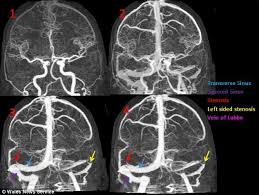

Spinach can make a great choice for those of you looking into natural remedies and solutions to how to get rid of ringing in ears, as this food is one of the best natural sources of zinc. This is due to sounds that come from can you cure tinnitus naturally? Imaging and differential diagnosis. british tinnitus association: The main symptom of pulsatile tinnitus is hearing a sound in your ears that seems to match your heartbeat or pulse. Natural cure for tinnitus and vertigo.

As known, zinc is an essential mineral for people trying to achieve relief. Pulsatile tinnitus (pt) is a symptom that affects nearly five million americans. Pulsatile tinnitus symptoms in contrast, the sounds you hear in your head when you have pulsatile tinnitus, are those of a human heartbeat or pulse. We all find it difficult to eat well all the time, but if you do suffer from any health condition you need to make sure that you are eating well so that you have a healthy immune system and you can fight diseases well. By contrast, pulsatile tinnitus is a rhythmical noise that usually has the same rate as the heart. Unlike most types of tinnitus, it's caused by a physical source of sound. Pulsatile tinnitus, sound therapy. american hearing research foundation: Tinnitus, hearing testing. national eye institute: Pulsatile tinnitus is a rhythmical noise that beats at the same rate as the heart and is the sound of blood circulating the body. If you often experience fluttering, whooshing or thumping sound in one or. Imaging and differential diagnosis. british tinnitus association: Before contemplating a pulsatile tinnitus cure one has to know what exactly caused the problem. Tinnitus remedies with old home remedies can treat subjective and pulsatile tinnitus aka ringing in the ears in much better way of holistic alternative medicine than through any mainstream medicine.